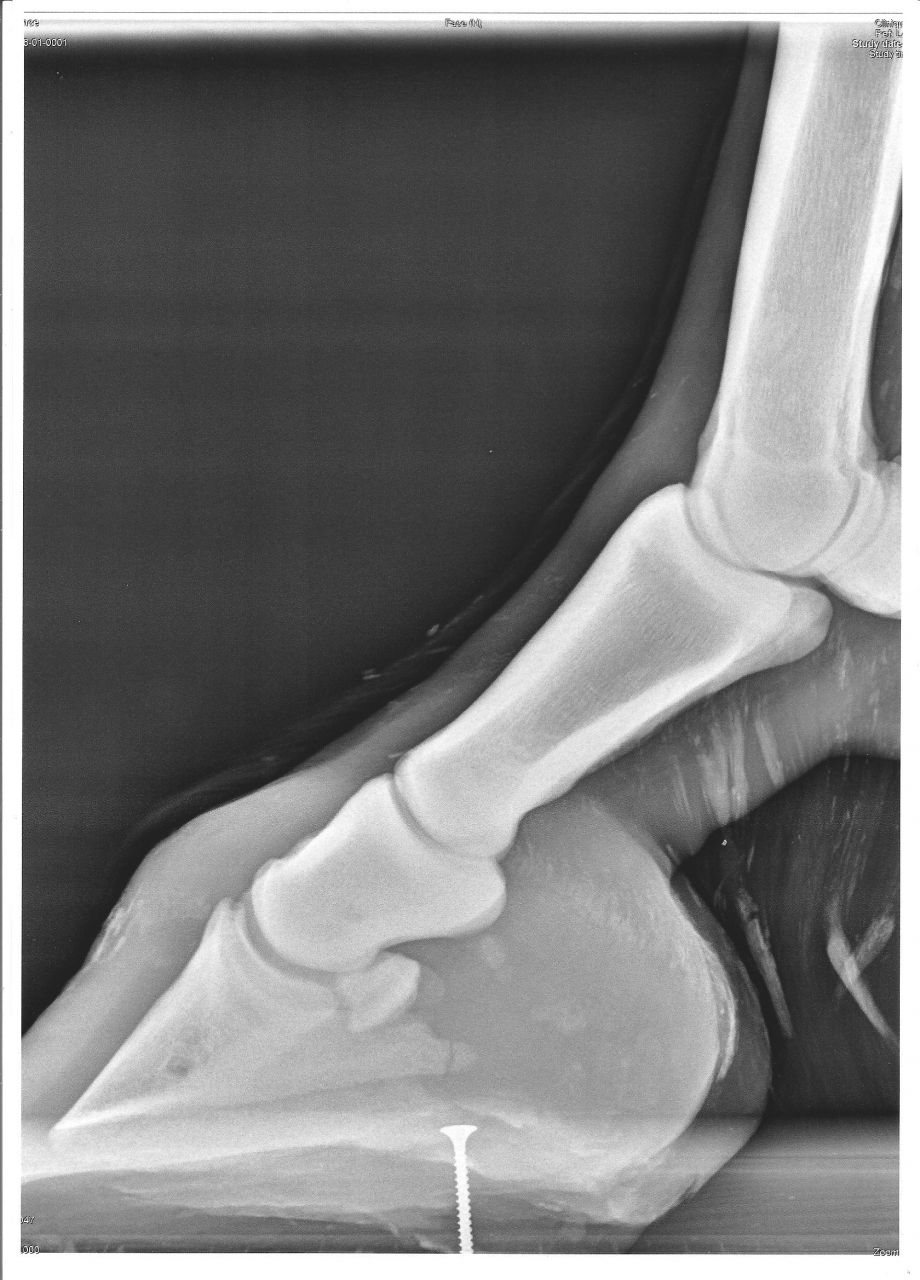

| Dire merci | Tout est dis dans le titre... Fracture du processus palmaire sur un Fijord de 9 ans, non ferré... Mais sa boiterie ne viendai pas de là, il ne réagit pas au test avec la pince... ( boiterie, sans doute, antérieure à la fracture d'après mon véto ) En attendant que mon véto me donne les consignes à suivre, je vais le mettre en box et s'il ne supporte pas, je le mettrai en petit parc... Je pence aussi faire venir le maréchal ferrant ( ferrure ? ) Je pence que c'est le mieux à faire en attendant... Je ne vais pas faire une bêtise ? Merci d'avance pour vos avis Voici les radios : ( c'est juste au dessu du vice ) ![]() ![]() |

| Dire merci | t'as pas des obliques??? ![]() pour diagnostiquer une fracture de P3, il faut parfois faire beaucoup de radios, parce que si on n'est pas pile poil dans l'angle, on peut la louper. en l'occurrence, 2 obliques en skyline sont un grand minimum pour diagnostiquer une fracture de processus palmaire... meme si on la voit pas mal sur la radio de profil (et ça ne réagit pas forcément à la pince ) |

| Dire merci | al non, j'ai que çà... une fracture de P3, P3 c'est le processus palmaire ? C'est comment 2 obliques en skyline ? |

| Dire merci | P3 c'est la 3ème phalange, soit l'os qui est dans le pied ![]() pour le reste, je laisserai AL répondre ![]() le fer boîte, est un fer qui limite au max les mouvements du pied (boite cornée), ceci afin de moins solliciter les parties abimées lors de leur cicatrisation |